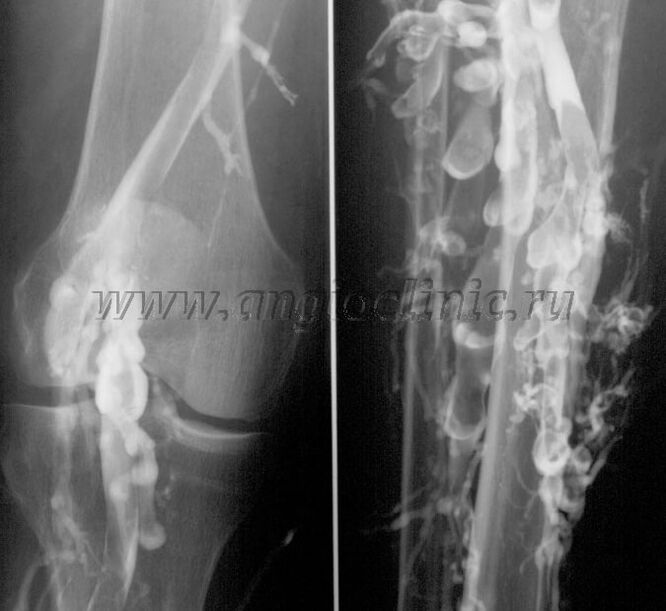

Contrast venography

Usually, ultrasound scanning is sufficient for a complete diagnosis of venous pathology, but in some cases it is necessary to study the relationship between the state of the deep and superficial venous system, especially in cases of relapses of varicose veins and secondary varicose veins.

To solve these problems, X-ray examination with contrast is used.The saphenous veins are punctured and contrast is given.The movement of the contrast is observed on the monitor of the X-ray machine and all necessary tests and projections are performed.Currently, venography for varicose veins is used very rarely.